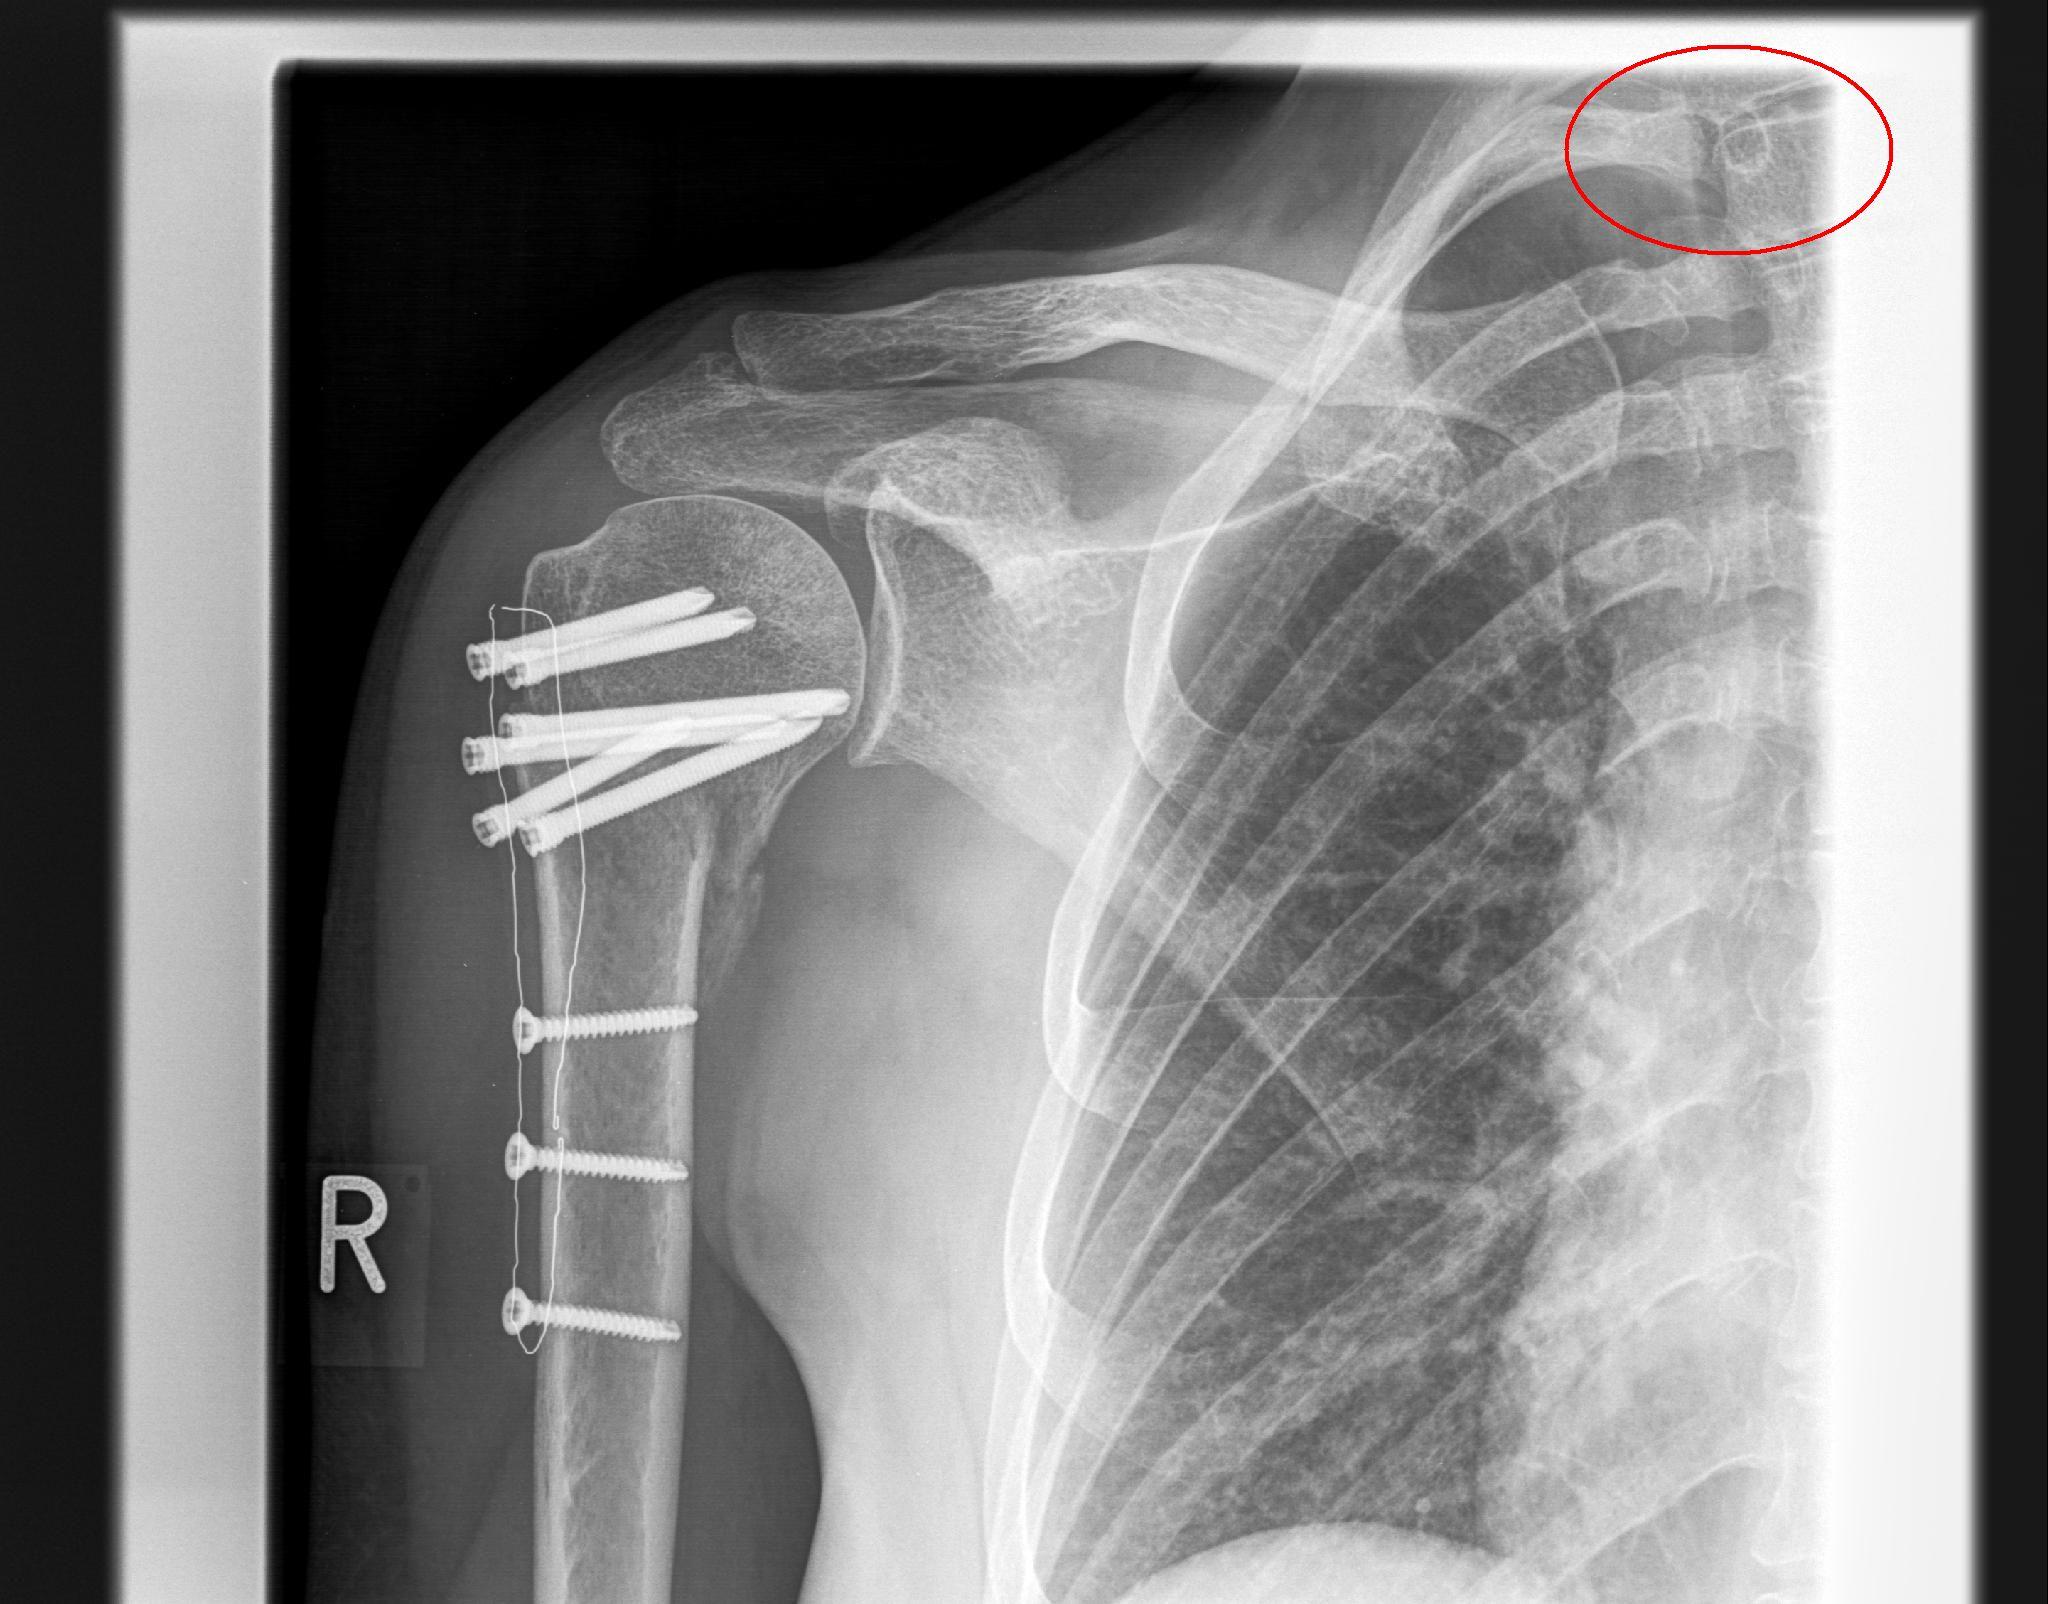

Es war eine mehrfragmentäre Humerusfraktur mit Head Split rechts, und der Bruch wurde durch eine Plattenosteosynthese fixiert (siehe Foto).

Aber meine Frage hier an die Experten ins Forum ist: soll ich die Platte entfernen lassen JA oder NEIN?

Mein Orthopäde sagt immer "wenn das meine Schulter wäre, ich würde es drin lassen, das Risiko das bei der Entfernung sich was verschlimmert wäre immer gegeben".

Ich fühle mich wie gesagt schon erheblich besser, aber die Stelle wo die Platte sitzt schmerzt bei manchen Bewegungen im Alltag, sogar beim Haare waschen. Oder auch wenn ich beim Autofahren einfach für ein Dankeschön-Handzeichen den Arm hebe tut es weh.

Meine Einstellung ist eigentlich das ich keine Fremdkörper im Körper haben möchte; aber natürlich habe ich auch keine Lust auf eine OP mit Vollnarkose und nochmal aufgeschnitten zu werden.

Ich hab schon eine zweite Meinung eingeholt und einen zweiten Orthopäden gefragt; der sagte auch die Platte bleibt drin wenn es nach ihm geht.

Meine Physiotherapeuten hingegen sagen immer das aus deren Erfahrung die Patienten eine erhebliche Verbesserung nach dem Entfernen verspüren.

das sieht tatsächlich schon ganz gut aus, wenn du mich fragst. Allerdings sieht man auch, dass die Schraubenköpfe einige mm aus dem Knochen hinaus ragen. Da kann ich mir gut vorstellen, dass du da schlecht drauf liegen kannst.

Was ich mir aber nicht vorstellen kann ist, dass das Schulterblatt-Problem damit zusammen hängt. Das Wegstehen des Schulterblattes ist meist eine muskuläre Störung, nämlich des "serratus anteriors" dieser wird wiederum vom "thoracicus longus" innerviert, das von den Halswirbeln C5-C7 entspringt. Das ganze nennt man "scapula alata"

Es gibt also eine Engstelle, dass den Nerv unter Druck setzt und somit den Muskel unterversorgt. Meistens wird diese Engstelle von einem Bandscheibenvorfall hervor gerufen! Aber auch von einer verschobenen 1. Rippe, dass den Nerven zwischen Schüsselbein und 1. Rippe einengt. Und genau das habe ich auf einem deiner Bilder entdeckt. Lass das mal checken!